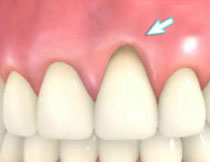

| 歯茎にプラーク(歯垢着が)と歯石の沈認められます。歯肉が腫れ、出血がありました。 | 歯科衛生士の治療と、ブラッシング技術の向上により、歯茎が引き締まり健康的な状態になりました。 | |